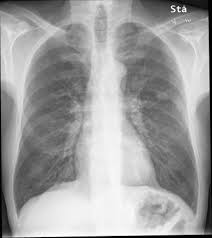

Early Detection Of Copd Is Important For Lung Cancer Surveillance European Respiratory Society from erj.ersjournals.com Copd has been linked to smoking, so simply not smoking, or quitting, will greatly reduce your risks of suffering from this condition. But, time is of the essence. When detected in its earliest stages, lung cancer can often be successfully treated and sometimes even cured. In this article they describe a variety of pulmonary conditions that can present with imaging features mimicking those of primary lung cancers. Pulmonary emboli are blood clots that have formed in other regions of the body and have then traveled to the lungs. However, the symptoms of lung cancer differ vastly from bronchitis which is one of the commonest affections of chronic smokers. Pancreatic cancer may also be misdiagnosed as gallstones or pancreatitis, or the inflammation of the pancreas. Can lung cancer be mistaken for copd?

Lung cancer develops due to the overgrowth of. This test can also be used to look for masses in the adrenal glands, liver, brain, and other organs that might be due to the lung cancer spread. A fungal infection called valley fever, which can cause mild to severe lung problems (including holes in the lungs), is often misdiagnosed because the symptoms can resemble those of the flu or. It can also show the size, shape, and position of any lung tumors and can help find enlarged lymph nodes that might contain cancer that has spread. Keep in mind that the symptoms of lung cancer in women. However, primary care physicians may have difficulty in classifying up to 20% of patients with obstructive pulmonary symptoms. That's because the symptoms of emphysema can easily conceal copd, and copd can conceal the presence of lung cancer. Despite the importance of all the causes mentioned by the authors, we would like to emphasize the relevance of fungal infections as an important cause of pulmonary nodules and masses that can mimic lung. That's because copd and lung cancer share common causes, including cigarette smoking and premature lung aging. Accurate diagnosis of copd is therefore critical. Furthermore, lung cancer symptoms, such as a persistent cough, back pain or weight loss, can resemble a cold or bronchitis and may not raise suspicions of lung cancer. Part of the dilemma for doctors is the significant overlap between copd symptoms and lung cancer symptoms. Other lung diseases, such as tuberculosis (tb) and chronic obstructive pulmonary disease (copd), also create a risk for lung cancer.